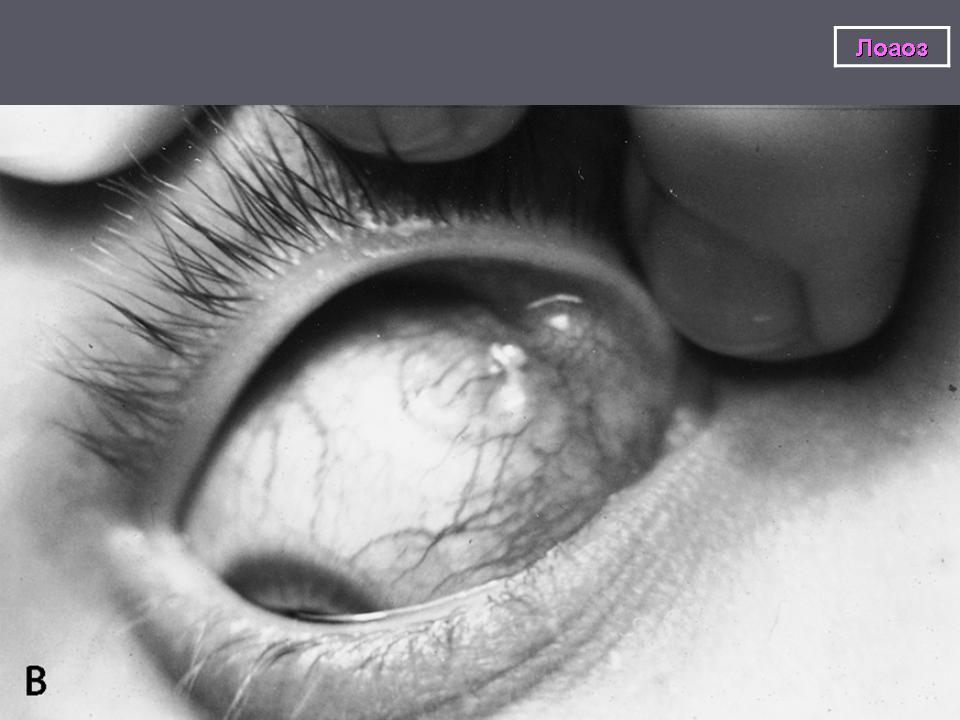

После внедрения возбудителя в организм человека в типичных случаях возникают общие аллергические симптомы: лихорадка, крапивница, зуд кожи, парестезии, которые вскоре купируются. Через 1-3 года развиваются характерные признаки лоаоза: «калабарский отек», подкожная и внутриглазная миграция зрелых гельминтов и гиперэозинофилия. Самым постоянным, обычным симптомом являются преходящие, ограниченные на разных участках туловища и конечностей отеки в виде куриного яйца или укуса осы, безболезненные; кожа над ними не изменена.

Перемещение червей под кожей вызывает зуд и жжение, передвижение их в уретре приводит к сильнейшим болям. Проникший под конъюнктиву паразит вызывает отек и гиперемию конъюнктивы, отек век, что нередко сопровождается сильной болью в глазу. Особенно опасные симптомы развиваются в связи с массовой гибелью микрофилярий, например при лечении. Отмечаются поражения почек с нефротическим синдромом, синдром менингоэнцефалита. Гибель зрелых паразитов и вторичная инфекция могут повлечь за собой развитие абсцессов различной локализации.